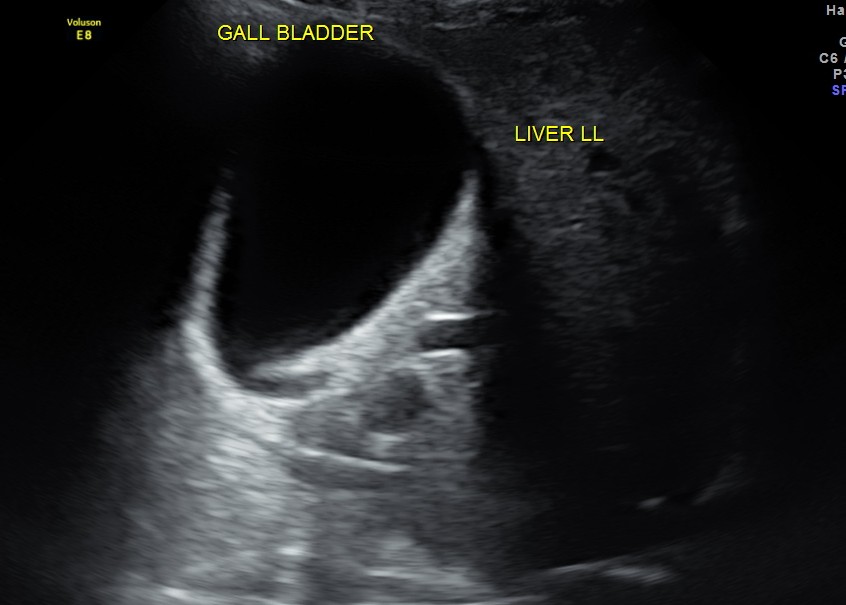

Liver, gall bladder , pancreas, spleen and the left kidney were normal . The prostate showed mild enlargement.